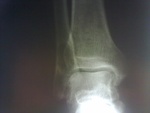

Вот рентгенограммы))))

Елена, я понимаю, что на снимке или КТ мы бы увидели: "четко ограниченный очаг остеолитической деструкции со вздутием и истончением коркового слоя". А возможно, увидели бы что-то еще. Понятно, что процесс доброкачественный, а уточнит его гистология. Но Вы действительно считаете, что требование перед МРТ выполнять рентгеновское исследование это каприз? Зря. Обычная рентгенография дала бы тот же диф. ряд, а при МРТ или КТ было бы понятнее как искать и что искать. Например, сделать КТ с контрастированием.

В остальном, после представления рентгенограмм, как говорят в математике: "что и требовалось доказать". Т.к. анализ рентгенограмм и МР-томограмм значительно сократил диф. ряд.